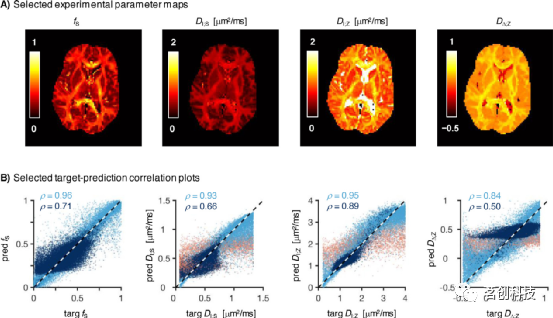

有趣的是,在不合理噪声的silico数据上训练的ANN可以获得比图5B中更平滑的体内地形图。图6显示了在S0处使用SNR∈[20,40]训练的RotInv网络获得的体内参数图,比图5的SNR低4倍。与相对更嘈杂的图5B相比,虽然人们倾向于选择图6中诱人的“稳健”地形图,但可以注意到低SNR RotInv网络导致目标参数和估计参数之间的相关性较弱(将图6的散点图与图5的散点图进行比较)。例如,基于SNN的DΔ;Z估计可能会产生一个看似稳健的平滑图,但仔细检查会发现WM和深度GM区域中的DΔ;Z估计等于目标DΔ;Z分布的平均值,并导致对地面真值的估计极其不准确。

图6.在数据集不足的情况下训练神经网络可能会产生看似合理的地图,但目标估计相关性较差。